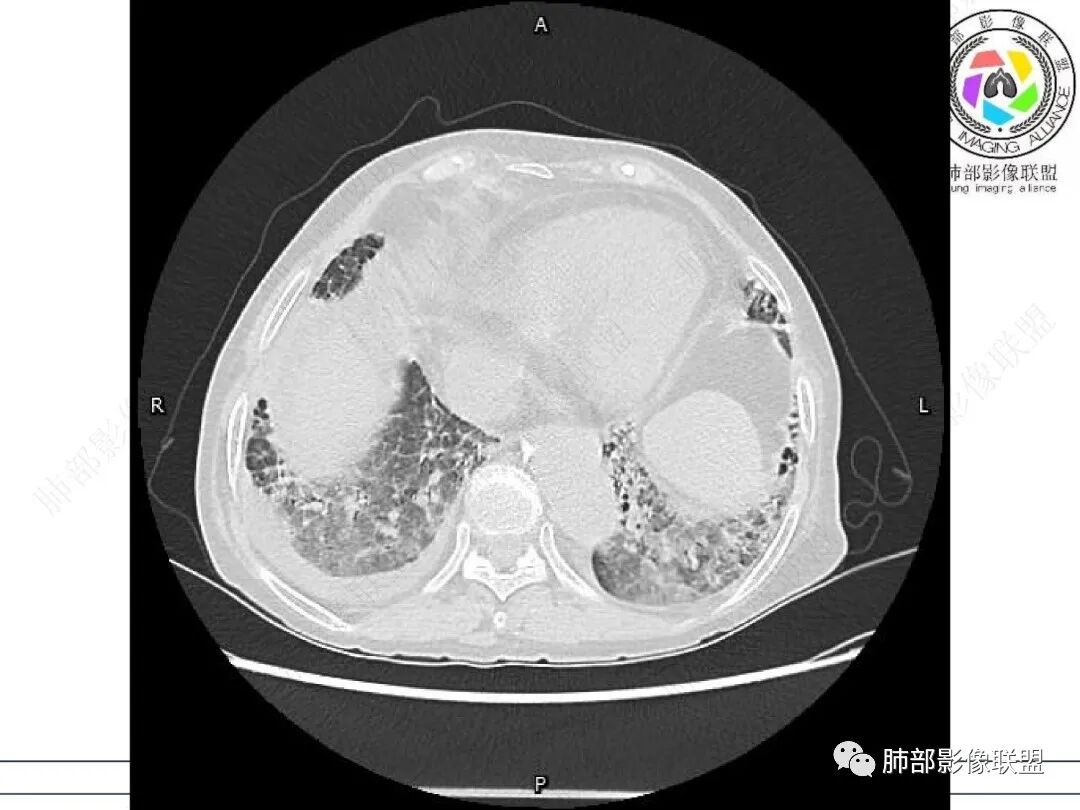

两肺叶后肋膈角区见多发蜂窝状结构破坏表现,双肺叶小叶间隔增厚,左肺上叶后段及舌段和右肺中叶胸膜炎性肉芽肿特点,双侧胸腔少量积液,有类风湿性关节炎治疗史,结缔组织相关性间质性肺病。

发热,有类风湿性关节炎、糖尿病基础病,长期口服激素及免疫抑制剂,双肺多发磨玻璃影及小叶间隔增厚,蜂窝影,支气管扩张考虑非特异性间质性肺炎存在,左肺上叶不规则结节影,周围长毛刺局部肺气肿,考虑慢性炎症,结合pct及crp升高考虑细菌感染,另真菌g升高考虑结合宿主因素,真菌感染需要积极排除。

老年,外阴溃疡加发热,感染指标明显有异常,血气分析,过度呼吸及低氧血症,宿主因素,糖尿病和激素,基础疾病RA。影像,双下肺体积有缩小,有蜂窝?双肺磨玻璃,多发结节,双侧胸水。树芽不明确。是否有旧片,这个患者有UIP背景,是否感染或者UIP急性加重,或者基础上合并肺栓塞及肺水肿?长期激素,没有提供CD4细胞亚群,存在2种情况,1,风湿病没有压制住,肺考虑CTD相关性间质改变,压制过猛,结合感染指标,奴卡是有可能的。激素加糖尿病,结核也带排,激素加磨玻璃加G实验阳性,PCP也带排,临床信息太少,进一步排查

老年女性,类风湿关节炎病史多年。发热。以两肺下叶为主弥漫磨玻璃及网格状透亮影,透亮度减低,局部小蜂窝状改变;两肺胸膜下散在几枚实性病灶;双侧胸腔积液。考虑RA-ILDNSIP

双下肺后肋膈角区见多发蜂窝,小叶间隔增厚,磨玻璃改变,,双侧胸腔少量积液,Crp明显升高,有类风湿性关节炎,糖尿病。甲氨蝶呤,托法替布治疗。会阴溃疡。考虑:1.免疫妥协2.pcp?巨细胞病毒?3.甲氨蝶呤致肺损伤?4.Ctd-ild.

两下肺多发蜂窝状表现,双肺小叶间隔增厚,双肺磨玻璃影及部分炎性肉芽肿表现,双侧胸腔积液,有类风湿性关节炎治疗史,结缔组织相关性间质性肺病。患者C反应蛋白和降钙素原都高,是否合并细菌感染

老年女性,外阴溃疡伴发热,有类风、糖尿病病史,血象及炎症指标高,G试验升高;影像:磨玻璃密度(中央分布为主)胸膜下蜂窝状改变心影增大、两侧胸腔少量积液;小叶间隔增厚,结节;考虑:1.中央分布为主的GGO需考虑:肺水肿、出血、PJP、肺泡蛋白沉着症;2.胸膜下间质性改变蜂窝肺,需考虑UIP、CTD-ILD,综合:两元论:CTD-ILD奴卡,或肺水肿

双肺下叶多发蜂窝影,双肺小叶间隔增厚,双肺磨玻璃影,双侧胸腔积液,有类风湿性关节炎,考虑结缔组织相关性间质性肺病,合并感染

①影像表现复杂:较弥漫间质性改变,对称磨玻璃密度为主,小叶间隔增厚,有一定重力分布趋势,未见明显纤维化,气囊及蜂窝位于肺边缘,未见典型“月弓征”。心脏影增大,双侧胸腔积液。

这即可见于间质性肺病,也可见于真菌感染(如PJP)、病毒感染,类风湿,以及肺水肿等等。

一般而言,如存在磨玻璃密度影浑浊,有重力分布趋势,肺表面蜂窝影,胸腔积液等等,并不常见于单纯PJP,除非其他因素叠加。

患者存在肺水肿应当是合理的解释。其他旁证还有,心脏影增大,肾小球滤过率降低,双侧胸腔积液等等……

上肺斑片影、结节影,夹杂纤维条索影,边界清楚,新旧不等,胸膜牵拉明显等等,符合较典型继发性肺结核表现,但它却未必是此次就医主要责任病原体!